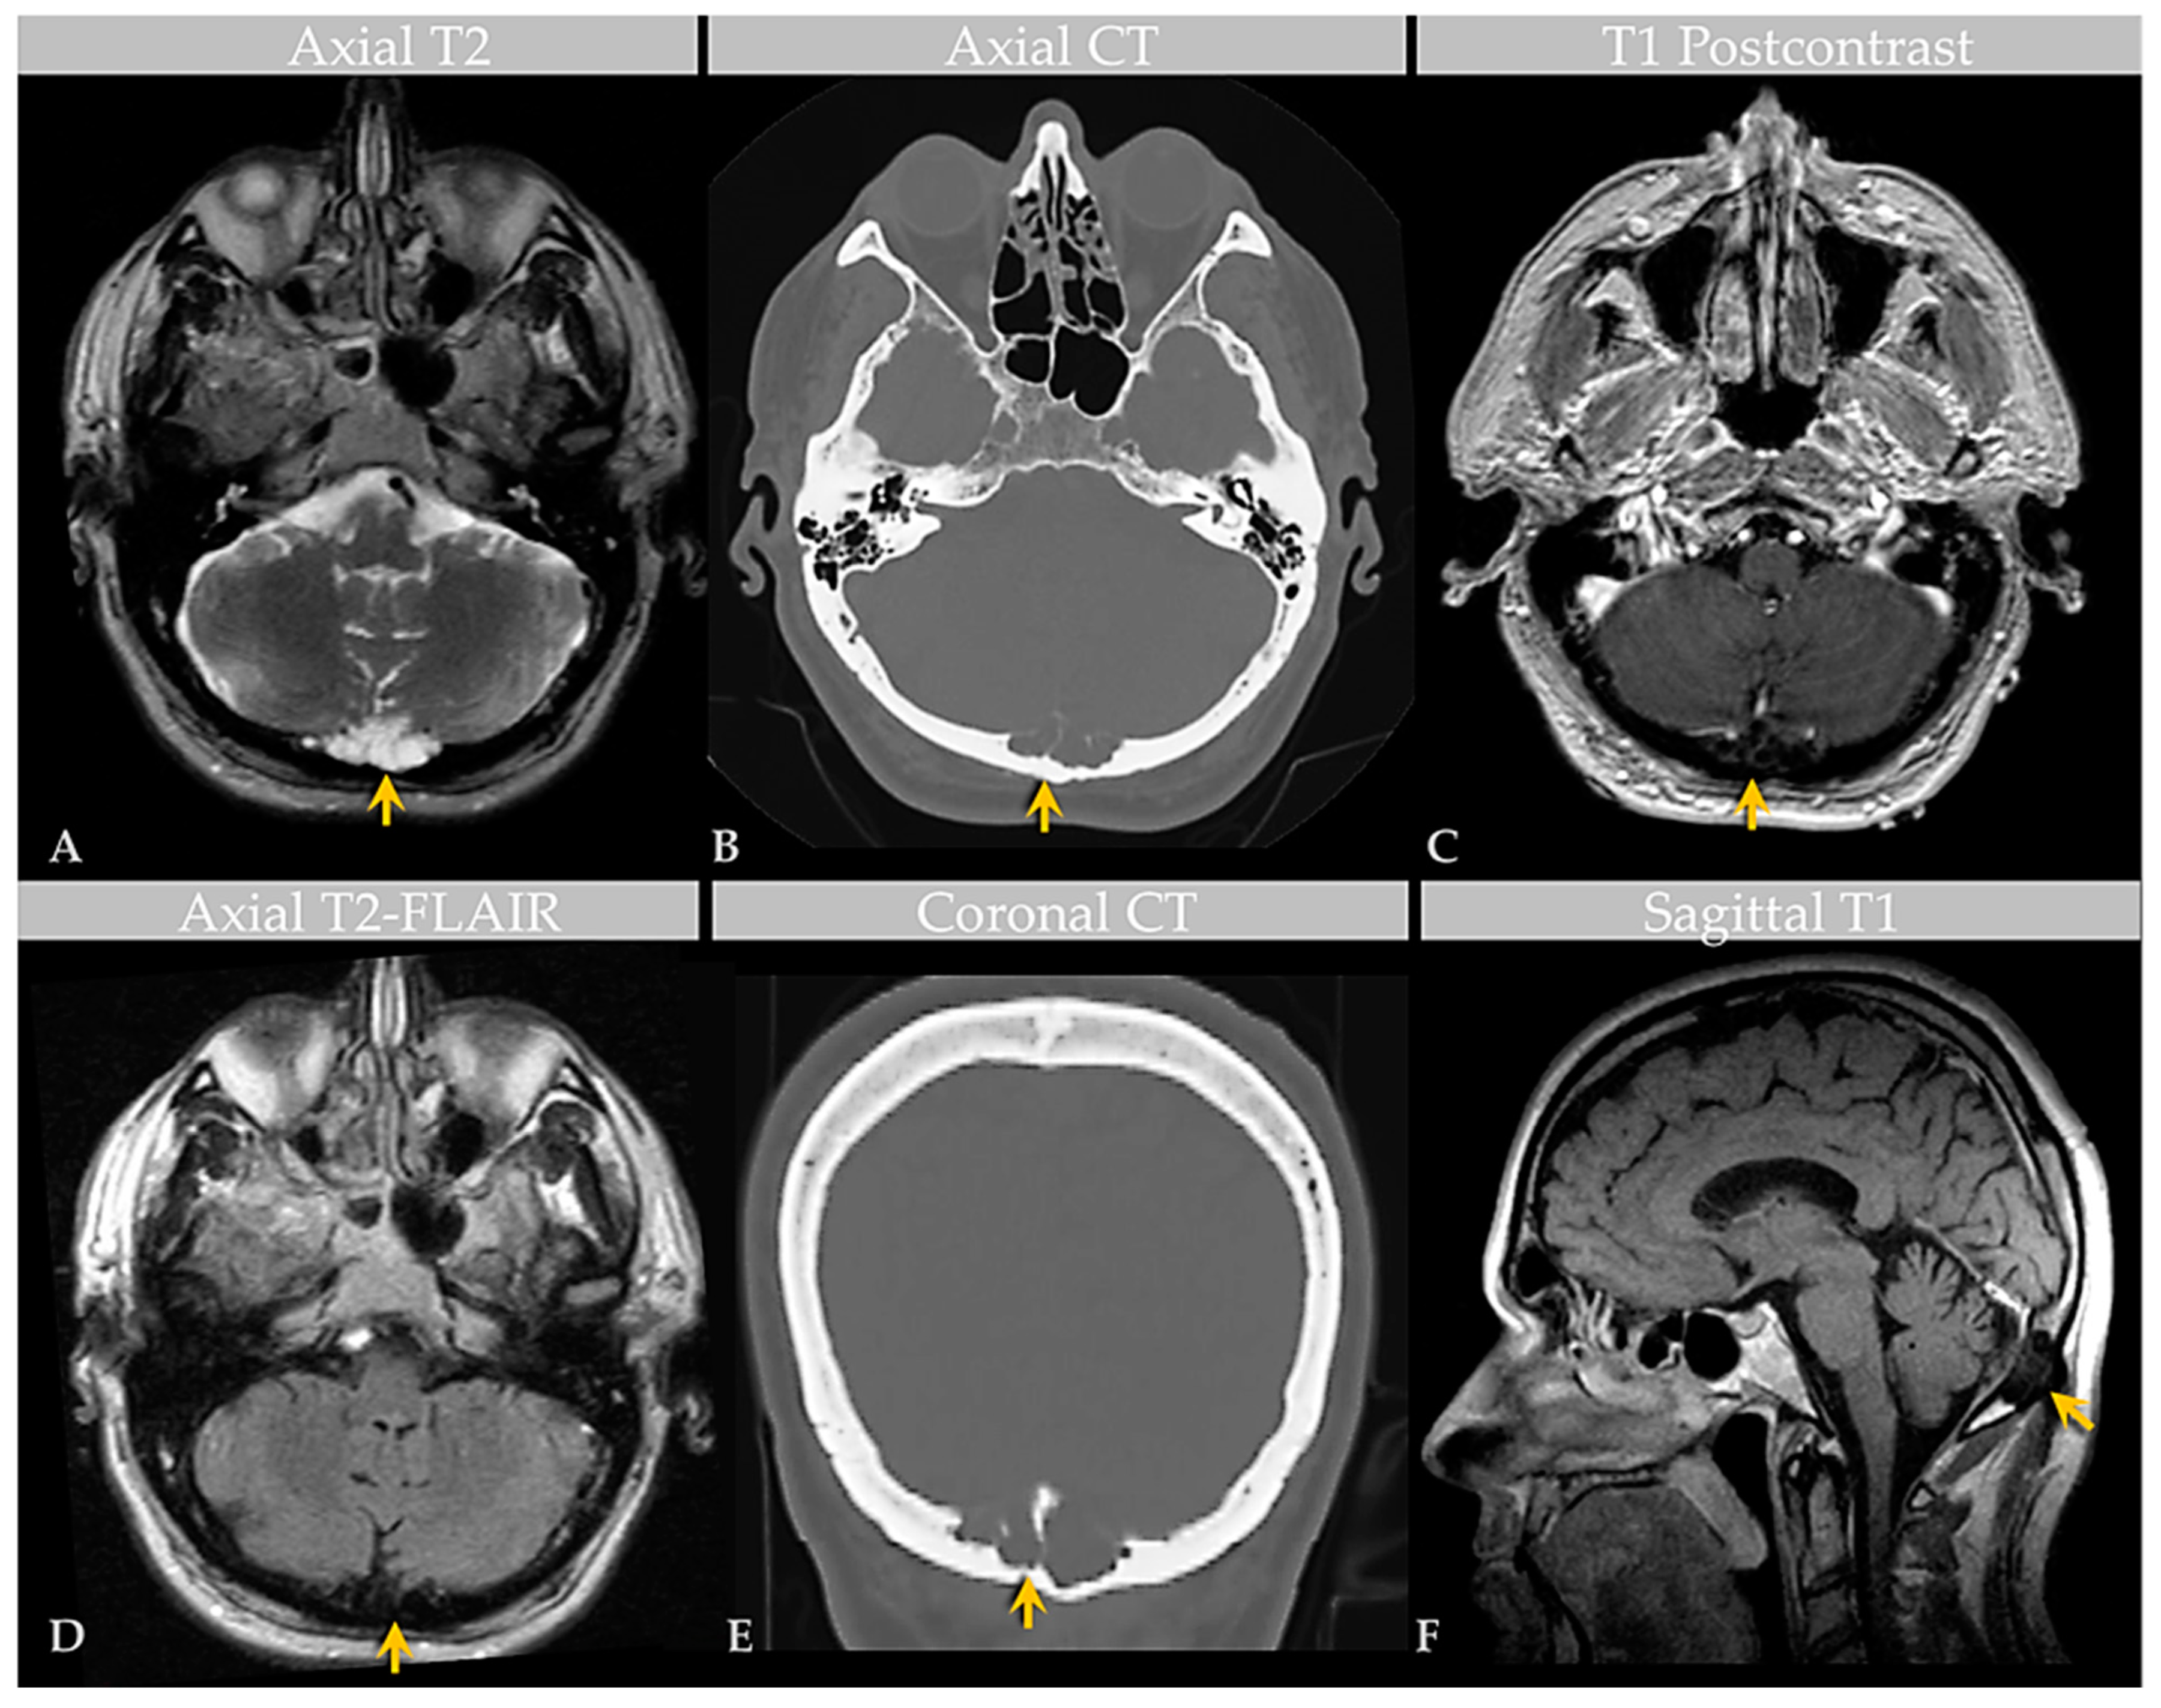

Brain MRI with and without contrast and noncontrast CT of the head (Figure 2) revealed a non-enhancing 3.6 × 1.3 × 1.8 cm abnormality that eroded the inner table of the occipital bone, causing lytic marrow expansion, extension through the dura and to the inion and the level of the torcula. Heterogeneous internal cystic-appearing MRI signal characteristics raised the possibility of an epidermoid cyst. There was no enhancing mass. MRI of the cervical spine did not reveal any abnormality to explain the patient’s symptomatology, though diffuse degenerative disease was appreciated. No definite cause for the radiculopathy was identified. A prior CT study documented the absence of the observed cranial lesion seven years prior to admission. To further evaluate the spinal cord, subarachnoid space, and associated structures, a CT myelogram was also performed (Figure 3) and revealed partial penetration of iopamidol (Isovue-M® 300) contrast tracer into the GAG interior, which demonstrated prominent internal soft tissue elements.

Figure 2. Case 2: Imaging of an individual with GAGs involving the confluence of sinuses. MRI (A) and CT (B) images show a GAG measuring over 3.6 cm centered in the region of the torcula horophili eroding through the diploic space and remodeling the outer cortex of the occipital bone (arrows). Note that the diploic space is expanded. There are thin, nonenhancing septae within the AG, as shown on postcontrast T1-weighted (C) and T2-FLAIR (D) MRI images, causing internal signal heterogeneity. Features are also demonstrated in the coronal CT image (E) and sagittal T1-weighted image (F). Images are from the same individual depicted in Figure 3.